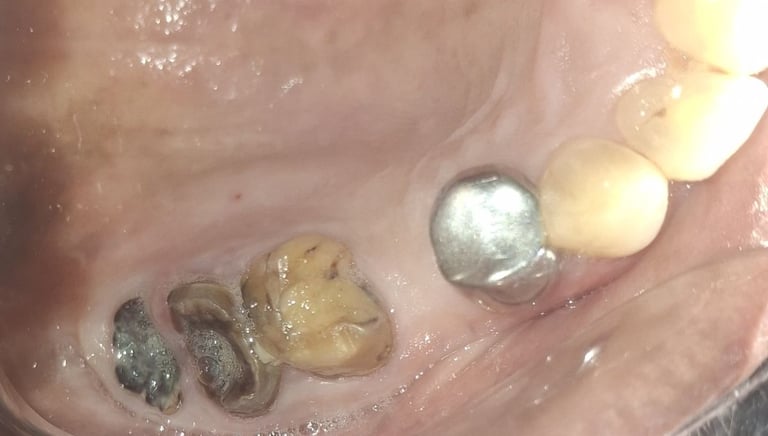

All images shown here represent real clinical cases of teeth extractions done at our dental clinic with patient consent.

Illustrative images and similar real clinical cases requiring tooth extraction